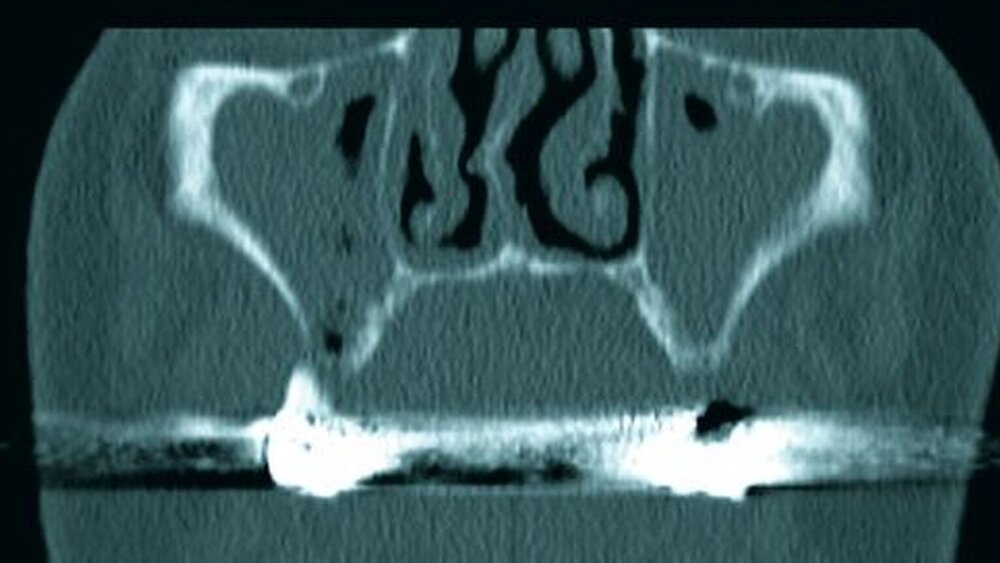

Die Computertomografie der Nasennebenhöhlen (NNH-CT) (nativ) zeigte dann das Ausmaß der knöchernen Destruktion. Neben der ausgedehnten generalisierten Nekrose des Oberkiefers konnte nebenbefundlich eine zystische Läsion im Bereich des Unterkiefers Regio 41 bis 45 diagnostiziert werden. Voraussichtlich ging diese vom Wurzelrest des Zahnes 41 aus. Weiterhin bestand eine totale Verschattung beider Sinus maxillaris und eine akzentuierte Lymphadenopathie in allen abgebildeten Leveln.